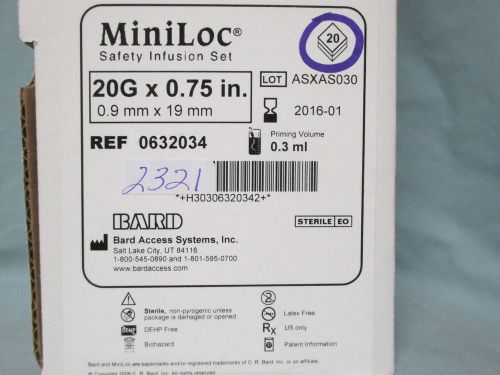

632034 Bard Access Systems Safety Set